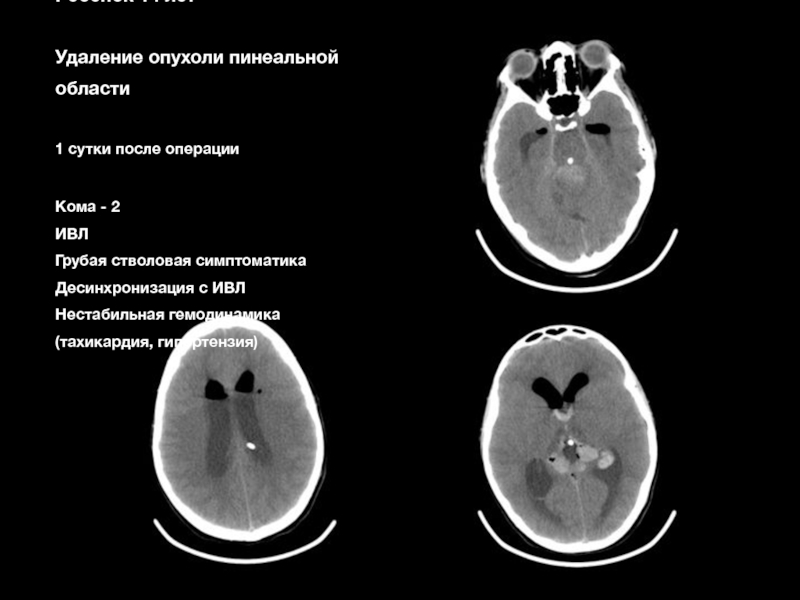

Слайд 68Женщина 39 лет

Клипирование гигантской

фузиформной

частично тромбированной

аневризмы М2 сегмента

СМА

с ЭИКМА

1 спт

Спутана, возбуждена

Речевые нарушения, гемипарез

Нарушения глотания

Нестабильная гемодинамика

Реинтубирована, ИВЛ

Седация

Стратегия

Дексдор

Женщина 39 летКлипирование гигантской фузиформной частично тромбированной аневризмы М2 сегмента СМА с ЭИКМА 1 сптСпутана, возбужденаРечевые нарушения,